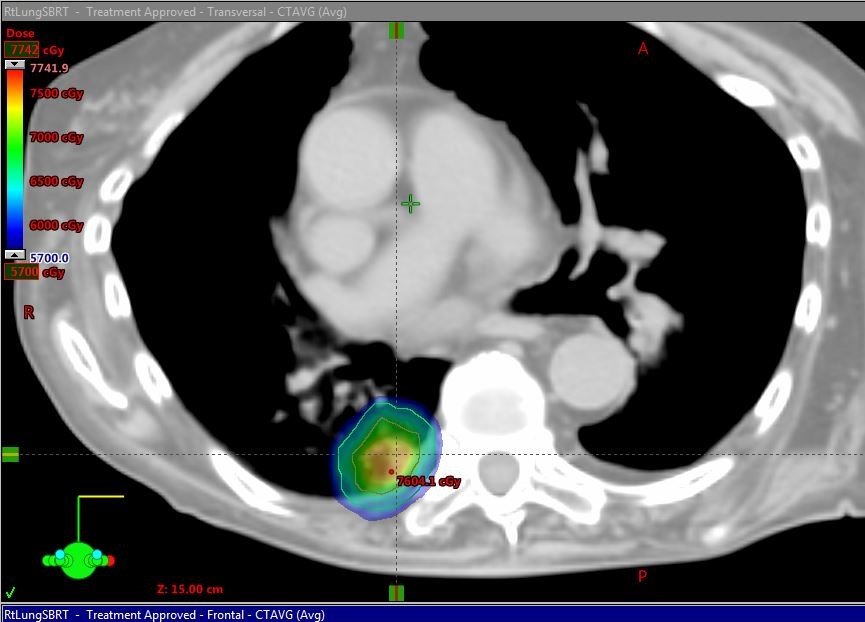

Lung irradiation has always presented a dosimetry problem with doses above 20Gy to the nearby healthy lung. VMAT has allowed higher doses to be delivered than previous generations of radiation dosimetry planning. Stereotactic body radiation therapy (SBRT) delivers high levels of radiation to the tumor.